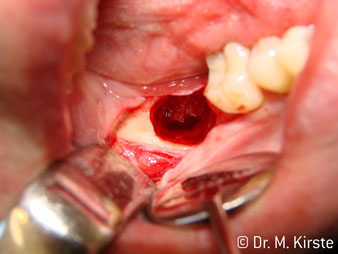

Die professionelle Lagergestaltung im Innenleben des Handstückkopfes garantiert einen ruhigen Lauf der Bohrer, bei der Zahn- oder Wurzelseparation (Abb. 4 - 9) zeigt sich ein beeindruckendes Schnittbild ohne Schlageffekte.

Abb. 4